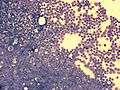

acute lymphoblastic leukemia (ALL), peripheral blood of a child, Pappenheim stain, magnification x100

bone marrow smear (large magnification) from a patient with acute lymphoblastic leukemia

bone marrow smear from a patient with acute lymphoblastic leukemia